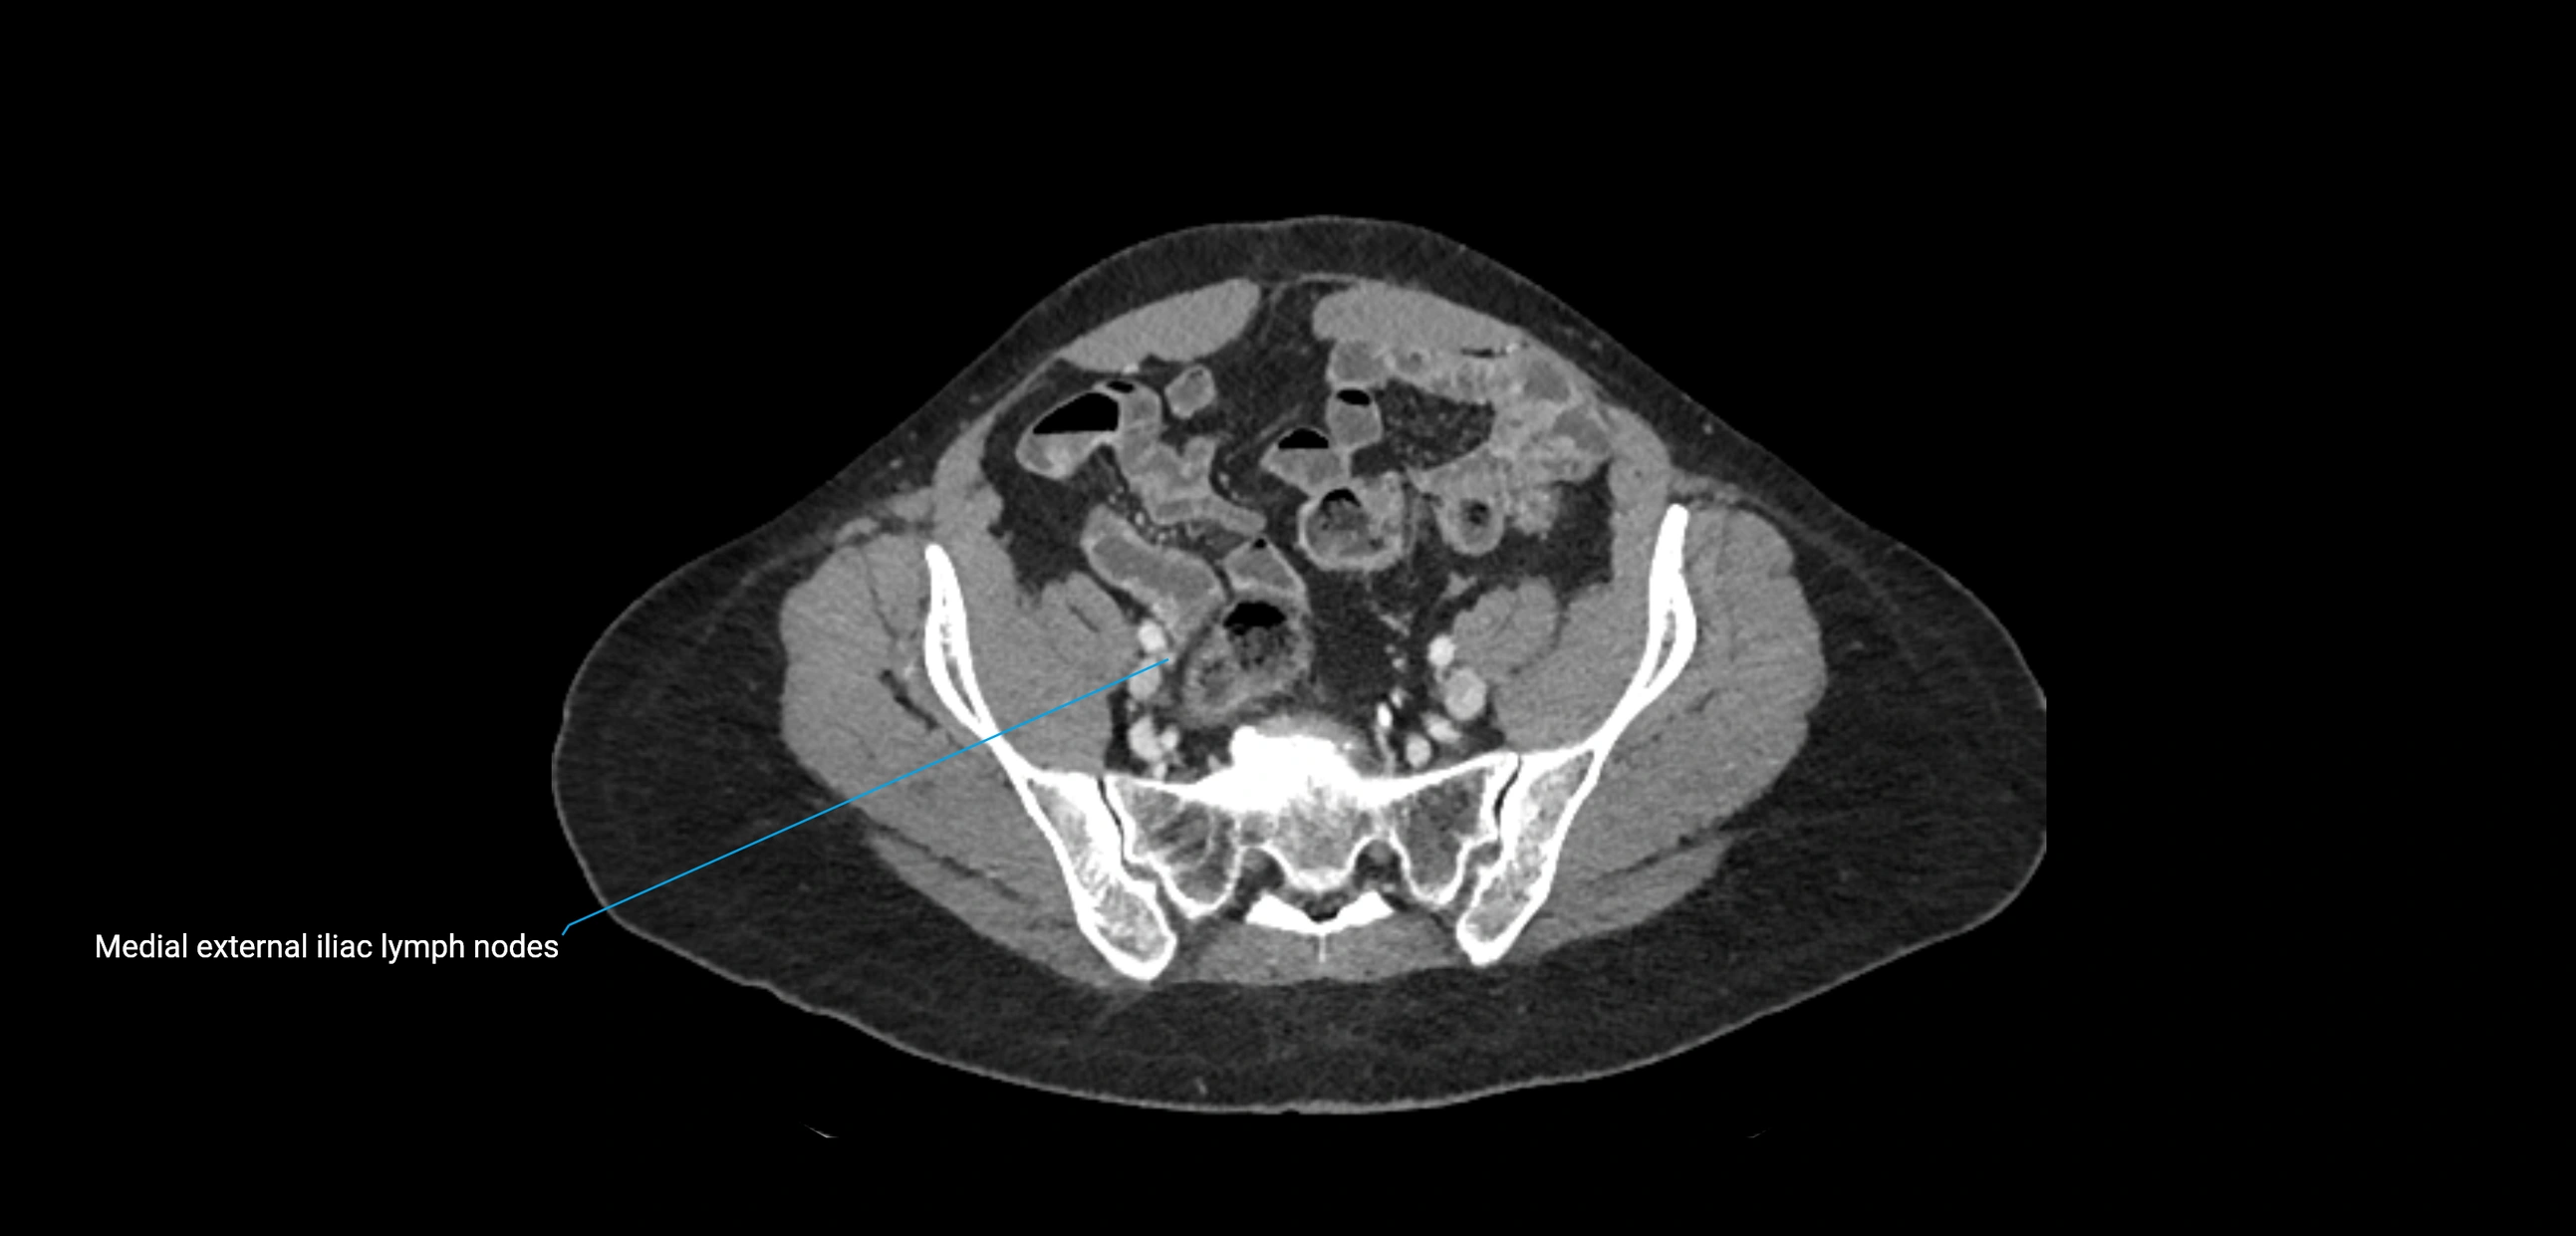

CT image

image